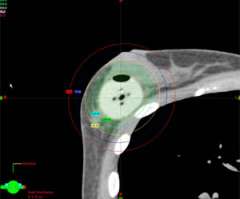

Below is an example of a case here at UCLA where we were able to spare the majority of the implant from receiving unnecessary radiation while achieving optimal coverage around the lumpectomy cavity.

Example of a partial breast case done at UCLA in a woman with breast augmentation who had a SAVI applicator placed. One can see that the distribution of the radiation dose as can be seen in the colored lines is focused around the lumpectomy cavity and that the majority of the implant (light grey) is spared from unnecessary radiation. A different view of the same patient with the SAVI applicator in the lumpectomy cavity just above the implant outlines in yellow.